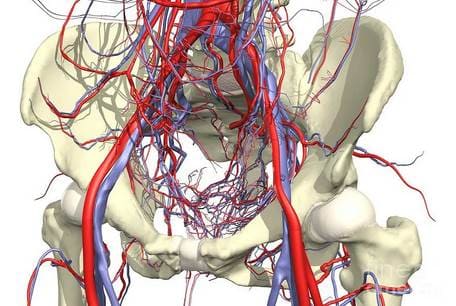

Tak więc stawy mają dość złożony system zaopatrzenia w krew, składający się z wielu cienkich naczyń włosowatych. Kiedy większość naczyń włosowatych zostaje zablokowana lub martwa, krew zaczyna płynąć przez te naczynia, które nie zostały uszkodzone. Prowadzi to do ich rozszerzenia i szybkiego zużycia z powodu ich przeciążenia. Ponadto takie zatkane naczynia krwionośne są bardziej wrażliwe na zmiany pogody. Boli tych, którzy są wrażliwi na pogodę.

Układ krążenia stawu jest układem złożonym.

Zdrowie stawów zależy bezpośrednio od ich

stanu.

Układ krążenia stawu jest układem złożonym.

Zdrowie stawów zależy bezpośrednio od ich

Podsumowując, możemy powiedzieć, że BÓL STAWÓW MOŻE ODNOSIĆ SIĘ DO USZKODZENIA UKŁADU KRĄŻENIA I POGORSZENIA PRZEPŁYWU KRWI. A jak niebezpieczne jest pogorszenie dopływu krwi do stawu? Bardzo niebezpieczne. Tu wszystko się zaczyna. Dopływ krwi zapewnia dopływ tlenu i składników odżywczych do narządów wewnętrznych, a także jest odpowiedzialny za usuwanie soli, produktów przemiany materii i innych „złych” substancji przez nerki lub wątrobę.